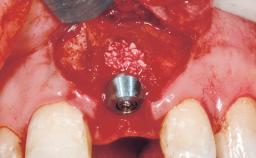

Late Placement of an Implant in a Maxillary Left Central Incisor Site

A 36-year-old female patient was referred for the replacement of the upper left central incisor (tooth 21), which had fractured. Although the tooth had been asymptomatic for many years, the crown began to loosen, at which time she presented to her dentist for an assessment. Teeth 21 and 22 had both been endodontically treated many years previously. She was a healthy individual and a non-smoker.

Bone Augmentation Horizontal|Staged

Augmentation Materials Xenogenous|Membrane

Soft Tissue Grafting Simultaneous

Bone Volume Deficient horizontally, requiring prior grafting